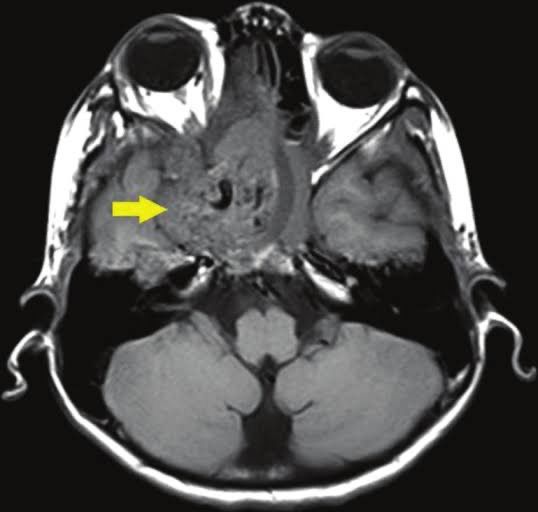

Juvenile nasopharyngeal angiofibroma is a benign tumour of nasopharynx found predominantly in young males. It is a locally aggressive tumour with severe tendency to bleed that’s why it is contraindicated to take a biopsy these cases. Clinically it produces symptoms of nasal obstruction, hypo-nasal voice, hearing loss and middle ear effusion during to Eustachian tube blockage. It may invade into adjacent structures and produce features of facial swelling, diplopia, nasal bridge broadening and cranial nerve palsies. Investigations includes imaging studies and angiography. Treatment is by surgical excision. Picture credit: Journal of clinical imaging science